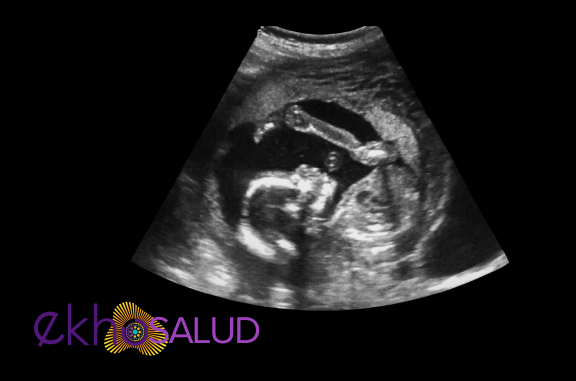

Este examen se realiza las primeras 11 semanas por vía transvaginal, y luego de este tiempo por vía transabdominal preferiblemente, a menos que se necesite evaluar cuello y placenta previa para lo cual esté indicada la vía transvaginal o la translabial. Útil para establecer la presencia de un embrión/feto con vida, evaluar su situación, presentación y el desarrollo de sus órganos, estimar el tiempo de gestación del embarazo, diagnosticar anomalías congénitas, así como la evaluación de la placenta, cordón y líquido amniótico según se realice en el 1er, 2do o 3er trimestre de gestación, a fin de determinar el crecimiento y bienestar fetal.

Preparación: No requiere ninguna preparación antes de las 11 semanas, de la 12 a la 16 semanas requiere tener vejiga llena, después de la semana 16 no es necesario tomar agua previo al estudio